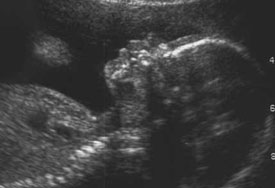

Los procedimientos por ultrasonido y por resonancia magnética (RMN) utilizan una forma de radiación “no-ionizante” muy diferente a los rayos X. Por este motivo, el ultrasonido se utiliza comúnmente durante el embarazo, sin que haya ningún caso conocido de daño al bebé por nacer debido a este procedimiento. A pesar de que no se usa tan frecuentemente como el ultrasonido, lo mismo aplica para la RMN.